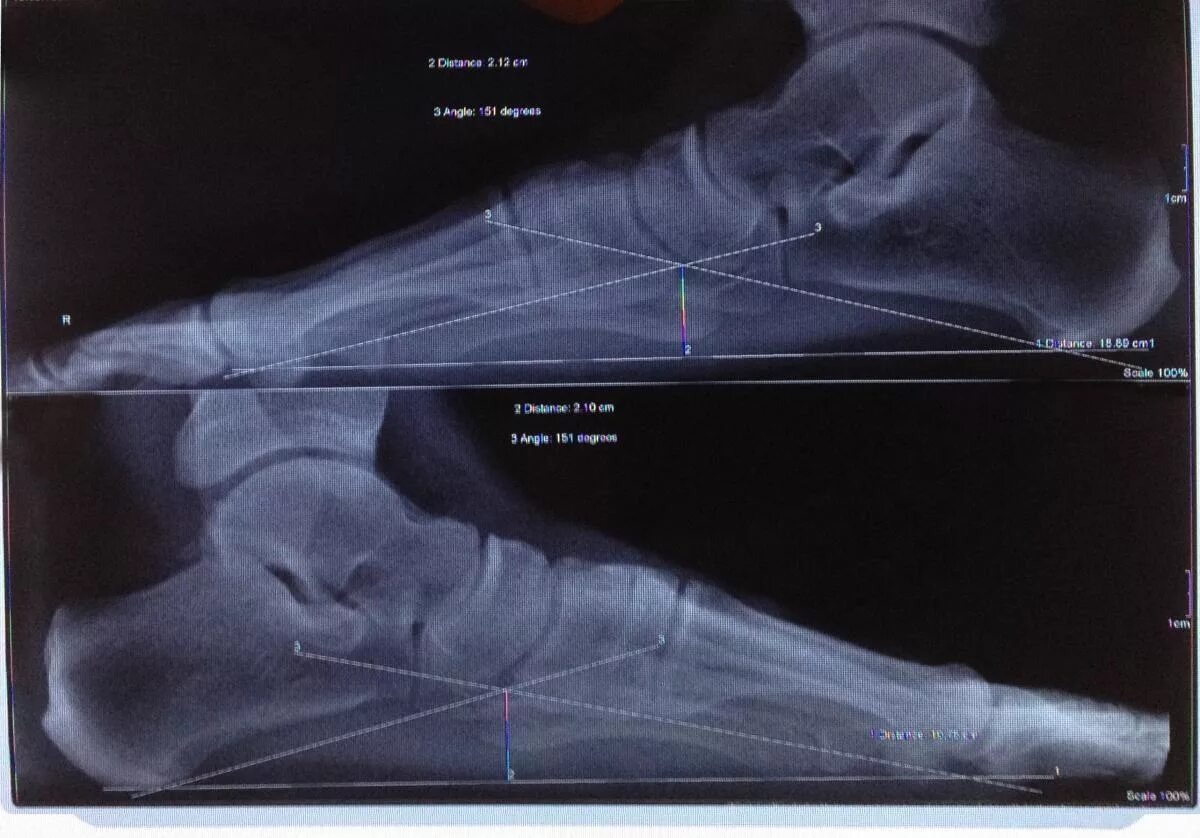

Плоскостопие – это **деформация стопы**, при которой свод (арка) опускается, и нога становится плоской.

### **2. Степени:**

- **1 степень** – почти незаметно, но ноги устают после ходьбы.

- **2 степень** – свод почти исчезает, боли усиливаются.

- **3 степень** – стопа полностью плоская, боли **не только в ногах, но и в спине**.